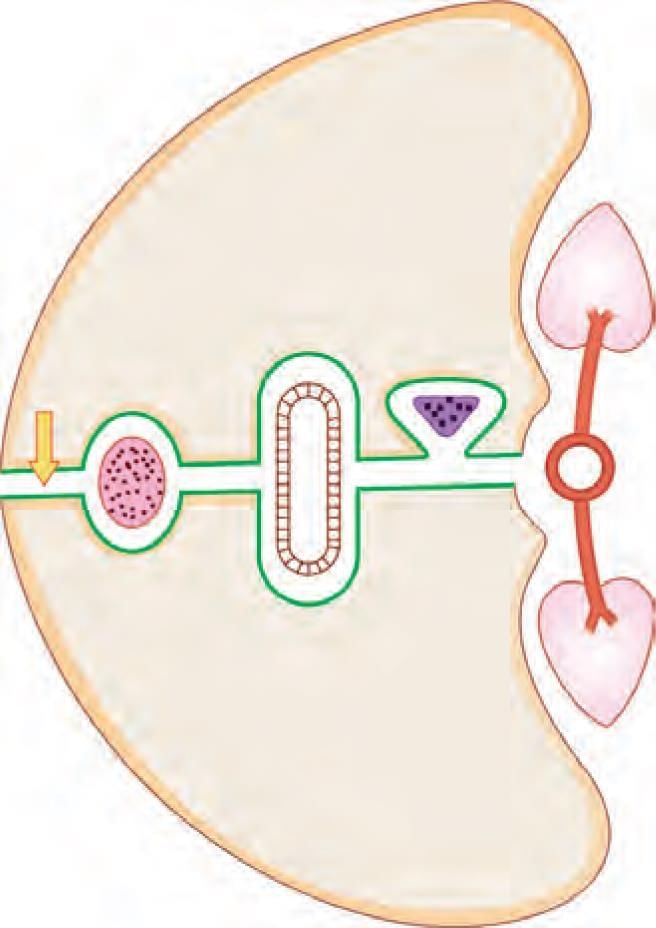

Choose the CORRECT matching pair for axillary lymph nodes in the given diagram: (INI-CET Nov 2022)